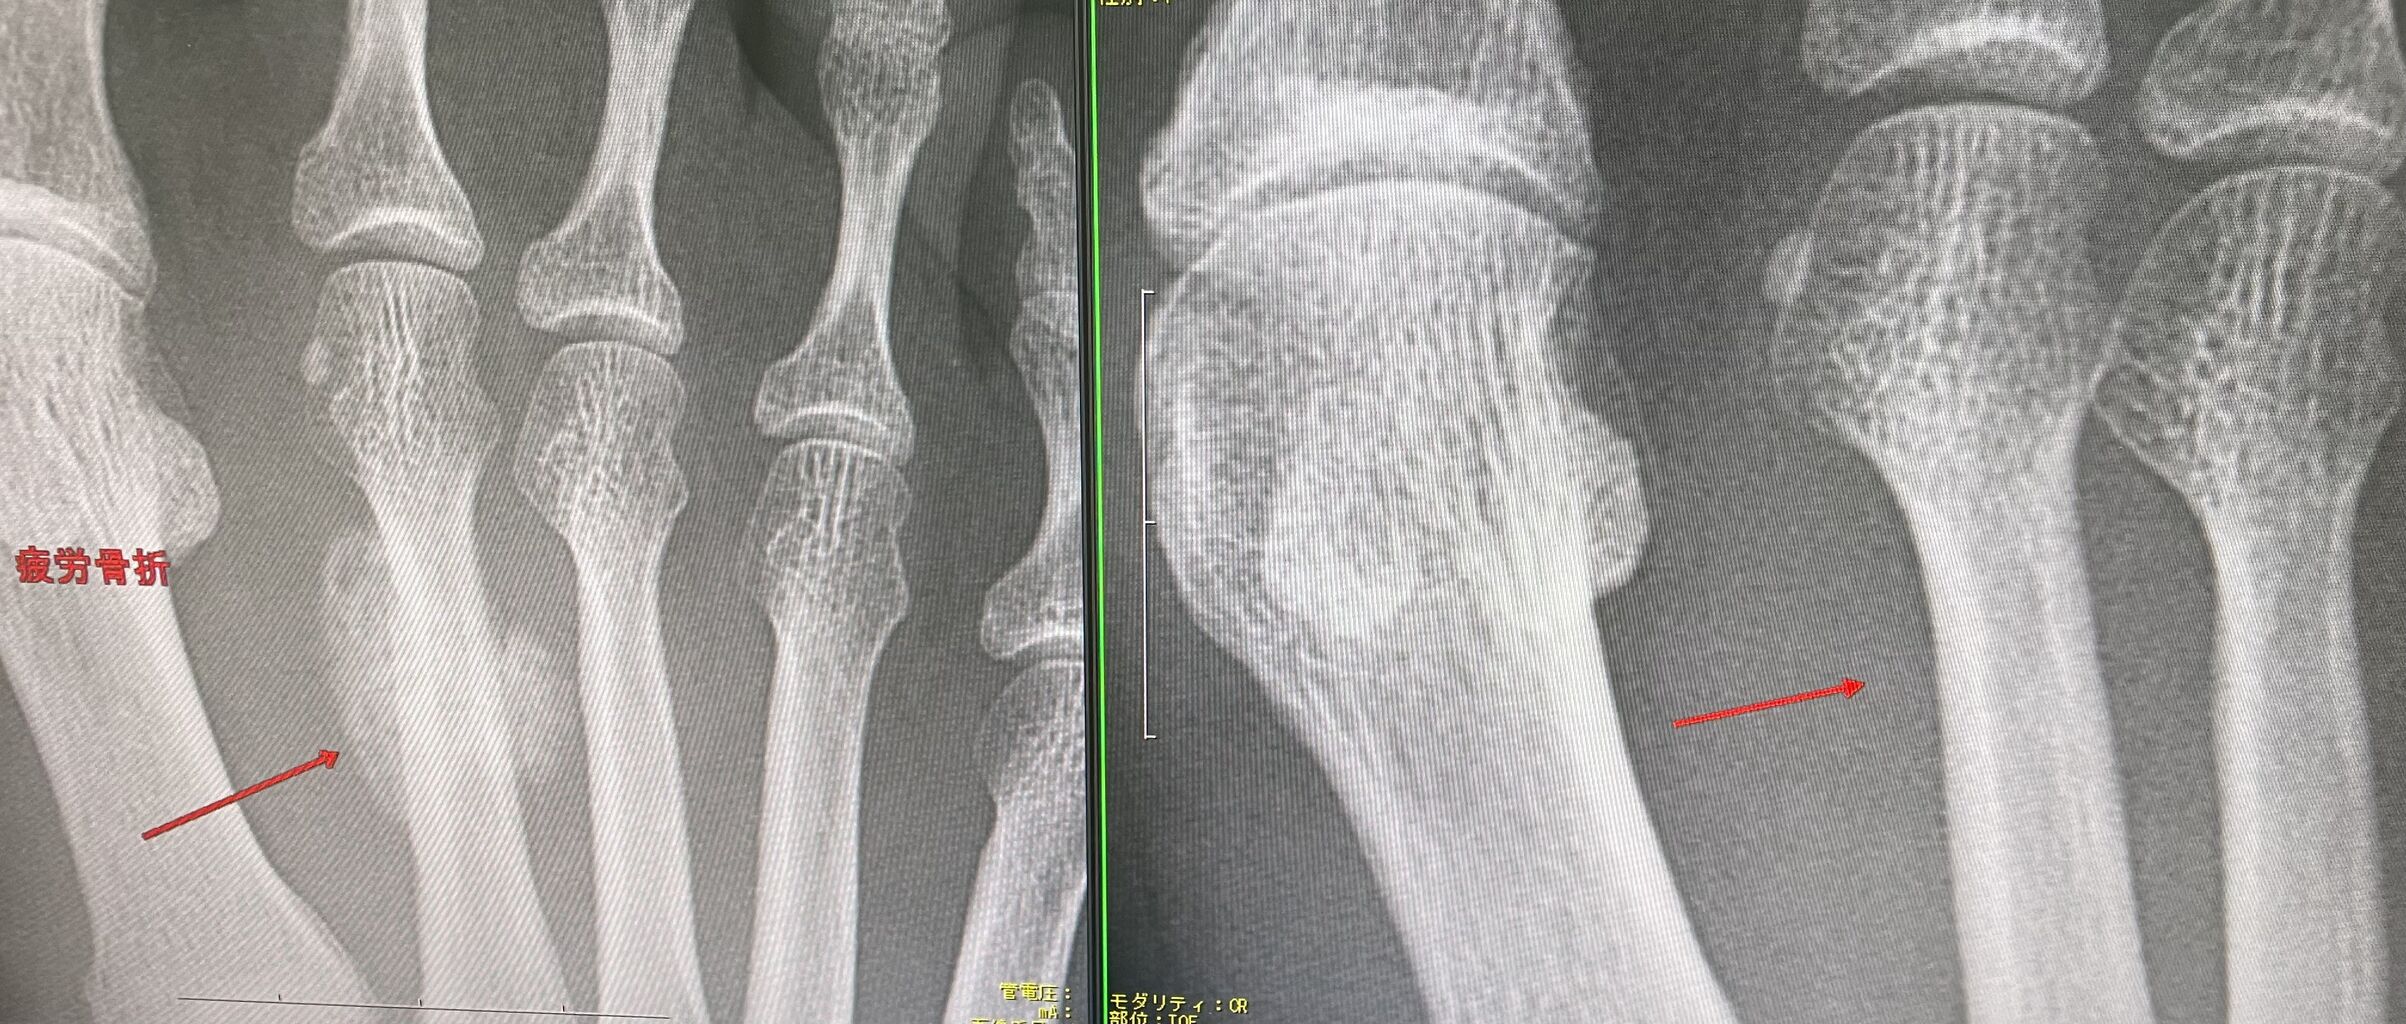

足の疲労骨折をかなり多く見られます